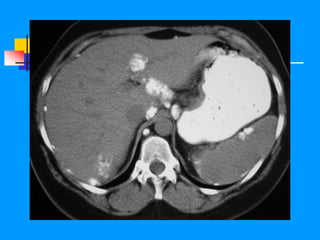

TAC

Líquido de ascitis

Ca de ovario

CÁNCER DE OVARIO TAC Líquido de ascitis Ca de ovario